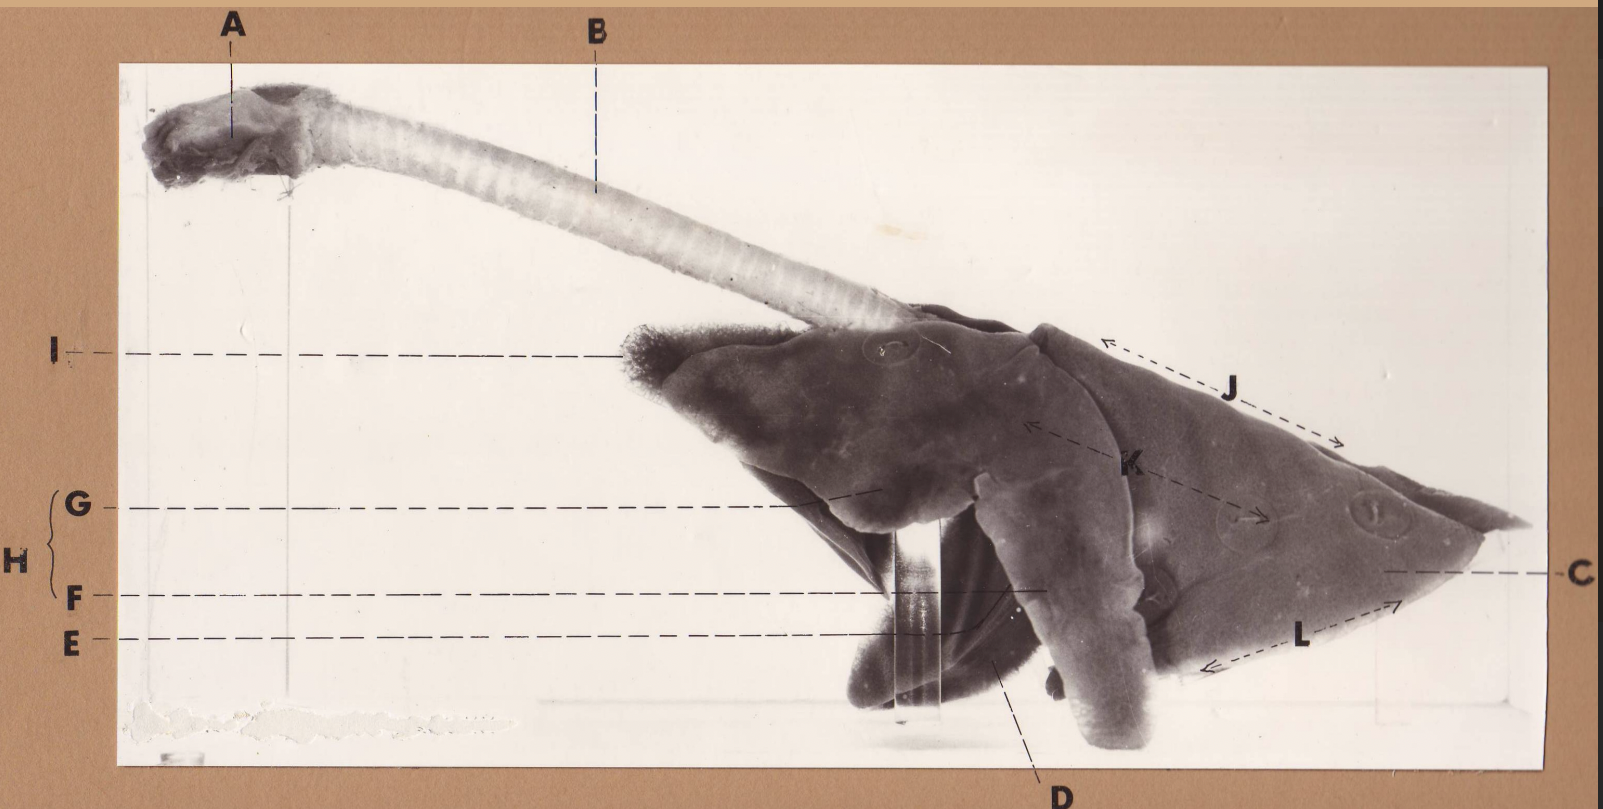

A

(cat larynx/trachea/lungs, L lateral)

larynx

B

(cat larynx/trachea/lungs, L lateral)

trachea

C

(cat larynx/trachea/lungs, L lateral)

caudal lobe

D

(cat larynx/trachea/lungs, L lateral)

middle lobe

E

(cat larynx/trachea/lungs, L lateral)

cardiac notch

F

(cat larynx/trachea/lungs, L lateral)

caudal segment

G

(cat larynx/trachea/lungs, L lateral)

cranial segment

H

(cat larynx/trachea/lungs, L lateral)

cranial lobe

I

(cat larynx/trachea/lungs, L lateral)

apex

J

(cat larynx/trachea/lungs, L lateral)

dorsal border

K

(cat larynx/trachea/lungs, L lateral)

costal surface

L

(cat larynx/trachea/lungs, L lateral)

basal border